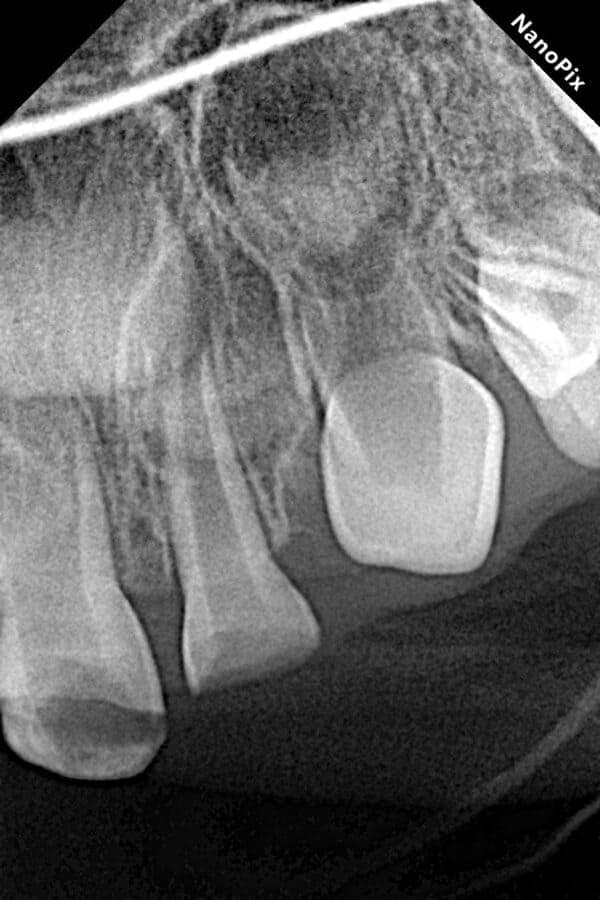

Поява перших постійних зубів, а це шості зуби, відбуваються, коли дитина ще не може, як слід провести їх гігієну та попіклуватись про їх здоров’я. Тому, на жаль вони і вражаються карієсом досить швидко. Пацієнт ще маленький – 6 років, а лікування потребує дорослого: зі знеболенням та ізоляцією. Саме таке і було проведене в даному випадку: зуб очищений від інфікованих тканин, відновлений фотополімерним матеріалом і готовий довго служити юному господарю.